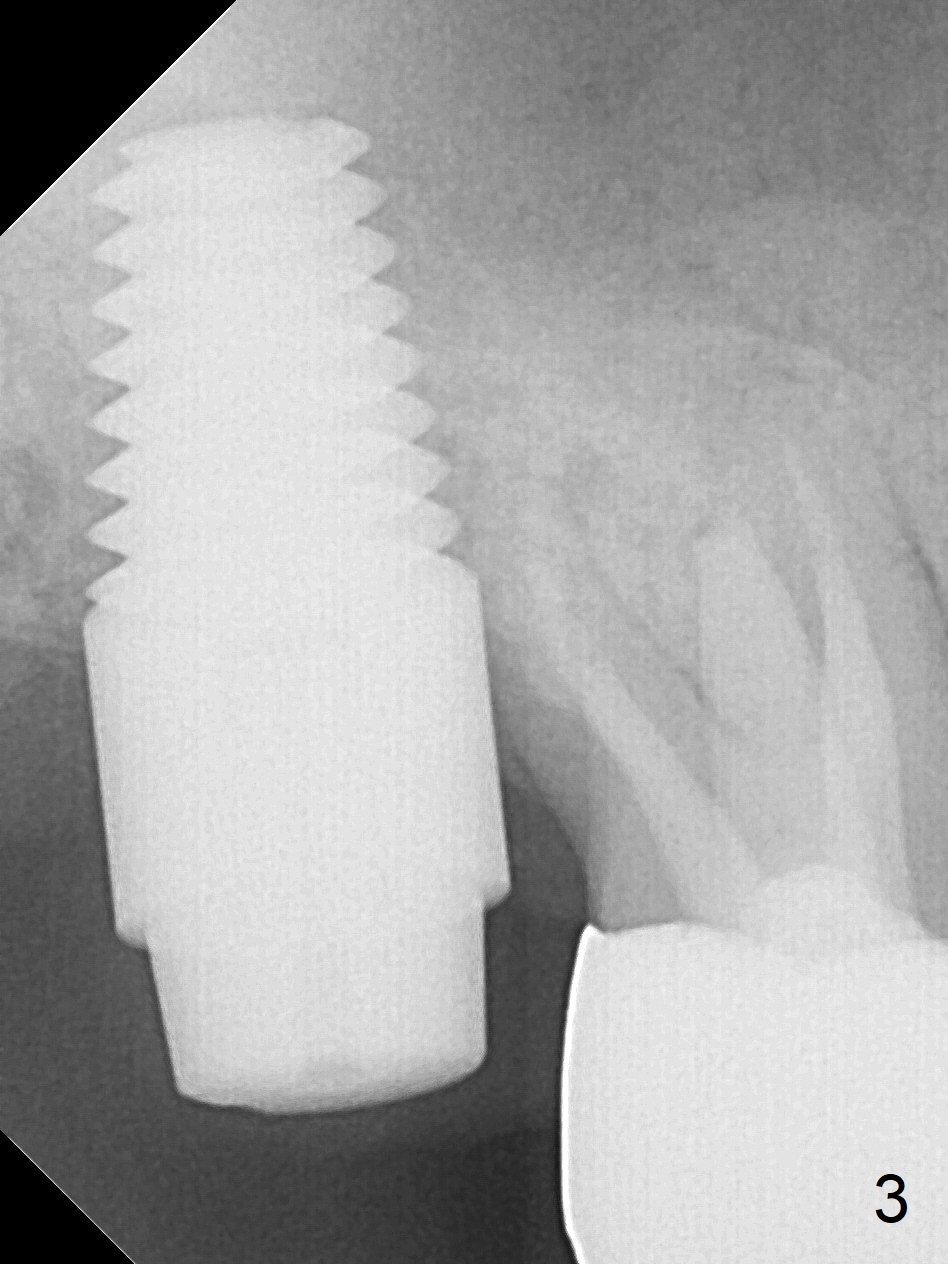

The tooth #2 is found to have fracture at extraction.  The buccal (B) socket (*) has more resorption than the palatal (P) one (Fig. A (S: sinus).  The buccal plate is also lower.  Osteotomy is initiated in the buccal slope of the septum with Magic Expanders (ME, 3-4.8 mm, Fig. B (red)), followed by Tatum tapered tap drills (Fig. C (green), Fig.1 (5x17 mm)).  As the diameter of ME and tap increases, the osteotomy is shifting buccally due to bone height discrepancy (Fig. C).  A Lindamann bur is used to remove the palatal bone (Fig. D (pink) and move the osteotomy palatally (Fig. E).  The coronal end of 7x14 mm tissue-level fixture (Fig.2) tilts buccally (Fig. F purple).  Insertion torque is 35/40 Ncm.  Prior to implantation, a piece of PRF membrane and allograft are pushed into the sinus.  A 6x3 mm abutment (Fig.2) is immediately placed to keep an immediate provisional, bone graft and collagen membrane in place.  Bone seems to have grown into the space between the implant threads 5.5 months postop (Fig.3).  There is no bone loss 2 years 2 months post cementation (Fig.4).